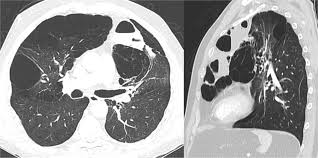

Bullous Lung Disease Ct Scan Ct Scan Machine